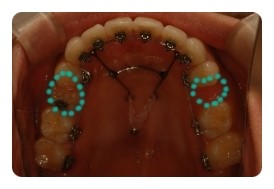

( 상악비교 )

▲ 발치 전 - 왼쪽유치 1차삭제, 오른쪽영구치 발치 예정

▲ 6월 - 스크류식립 후 본격적으로 상악당기기 1개월차

▲ 8월 - 3개월차

▲ 10월 - 5개월차

조신하지못한 저의 잦은 어금니 브라켓탈락 ㅠㅠ 에도 불구하고 잘 이동하고 잇는듯해요